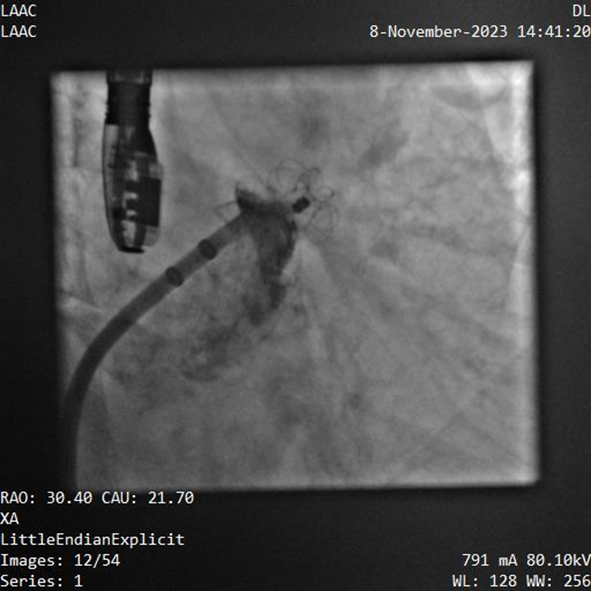

該例患者為男性58歲,陣發(fā)性房顫,9個(gè)月前突發(fā)急性腦梗死,3月前曾行房顫射頻消融術(shù)。2023年11月經(jīng)胸超聲心動(dòng)圖示左房內(nèi)徑46mm,經(jīng)食道超聲心動(dòng)圖示左心房及左心耳內(nèi)未見血栓形成,CHA2DS2-VASc評(píng)分3分,HAS-BLED評(píng)分2分。DSA測得左心耳開口直徑約23mm,錨定區(qū)域約18mm。

葛均波院士、周達(dá)新教授等經(jīng)詳細(xì)評(píng)估和討論后,認(rèn)為該受試者需要植入固定部20mm、封堵盤28mm的左心耳封堵器,為非常規(guī)固配規(guī)格,SimuLock的可選配組裝式設(shè)計(jì)精準(zhǔn)滿足患者需求。

手術(shù)過程順利,通過植入非常規(guī)固配規(guī)格的固定部20mm、封堵盤28mm的左心耳封堵器,實(shí)現(xiàn)左心耳完全封堵,達(dá)到手術(shù)預(yù)期效果,再次體現(xiàn)產(chǎn)品獨(dú)特的設(shè)計(jì)創(chuàng)新優(yōu)勢(shì)。

器械釋放后造影示封堵器展開良好,封堵完全